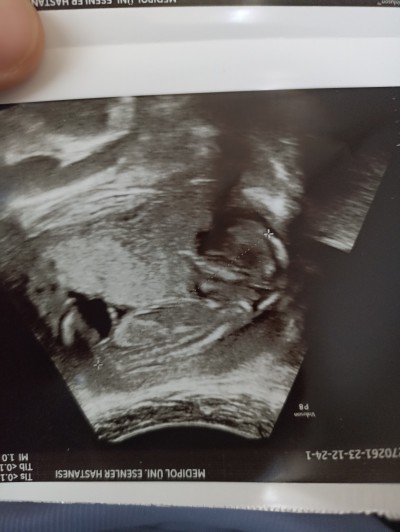

cinsiyet tahmin edebilen var mı arkadaşlar

Gebelik haftası 14.4

Bana kiz gibi geldi canım sağlıkla gelsin inşallah çünkü benimki de bu tarzda doktor kiz gibi dedi

Kıza benzettim hayırla sağlıkla gelsin :)

Kız ordaki çıkıntı pipisi gibi geldi bana ,çünkü benimde öyleydi hemen hemen, Rabb'im gönlüne göre versin inşallah canım

Kız bebek büyük ihtimalle